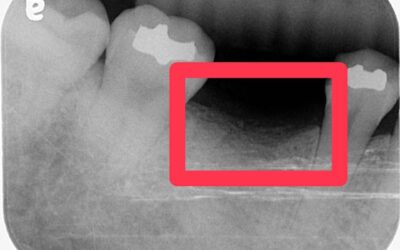

一開始只是單純的根管治療,沒想到過程中發生器械分離的併發症,導致牙根受損,最終只能走向拔牙 → 改做植牙...